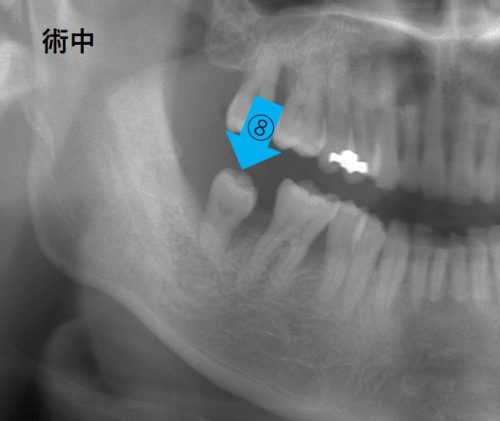

← 201.親知らずの移植!歯周病の歯を救え!